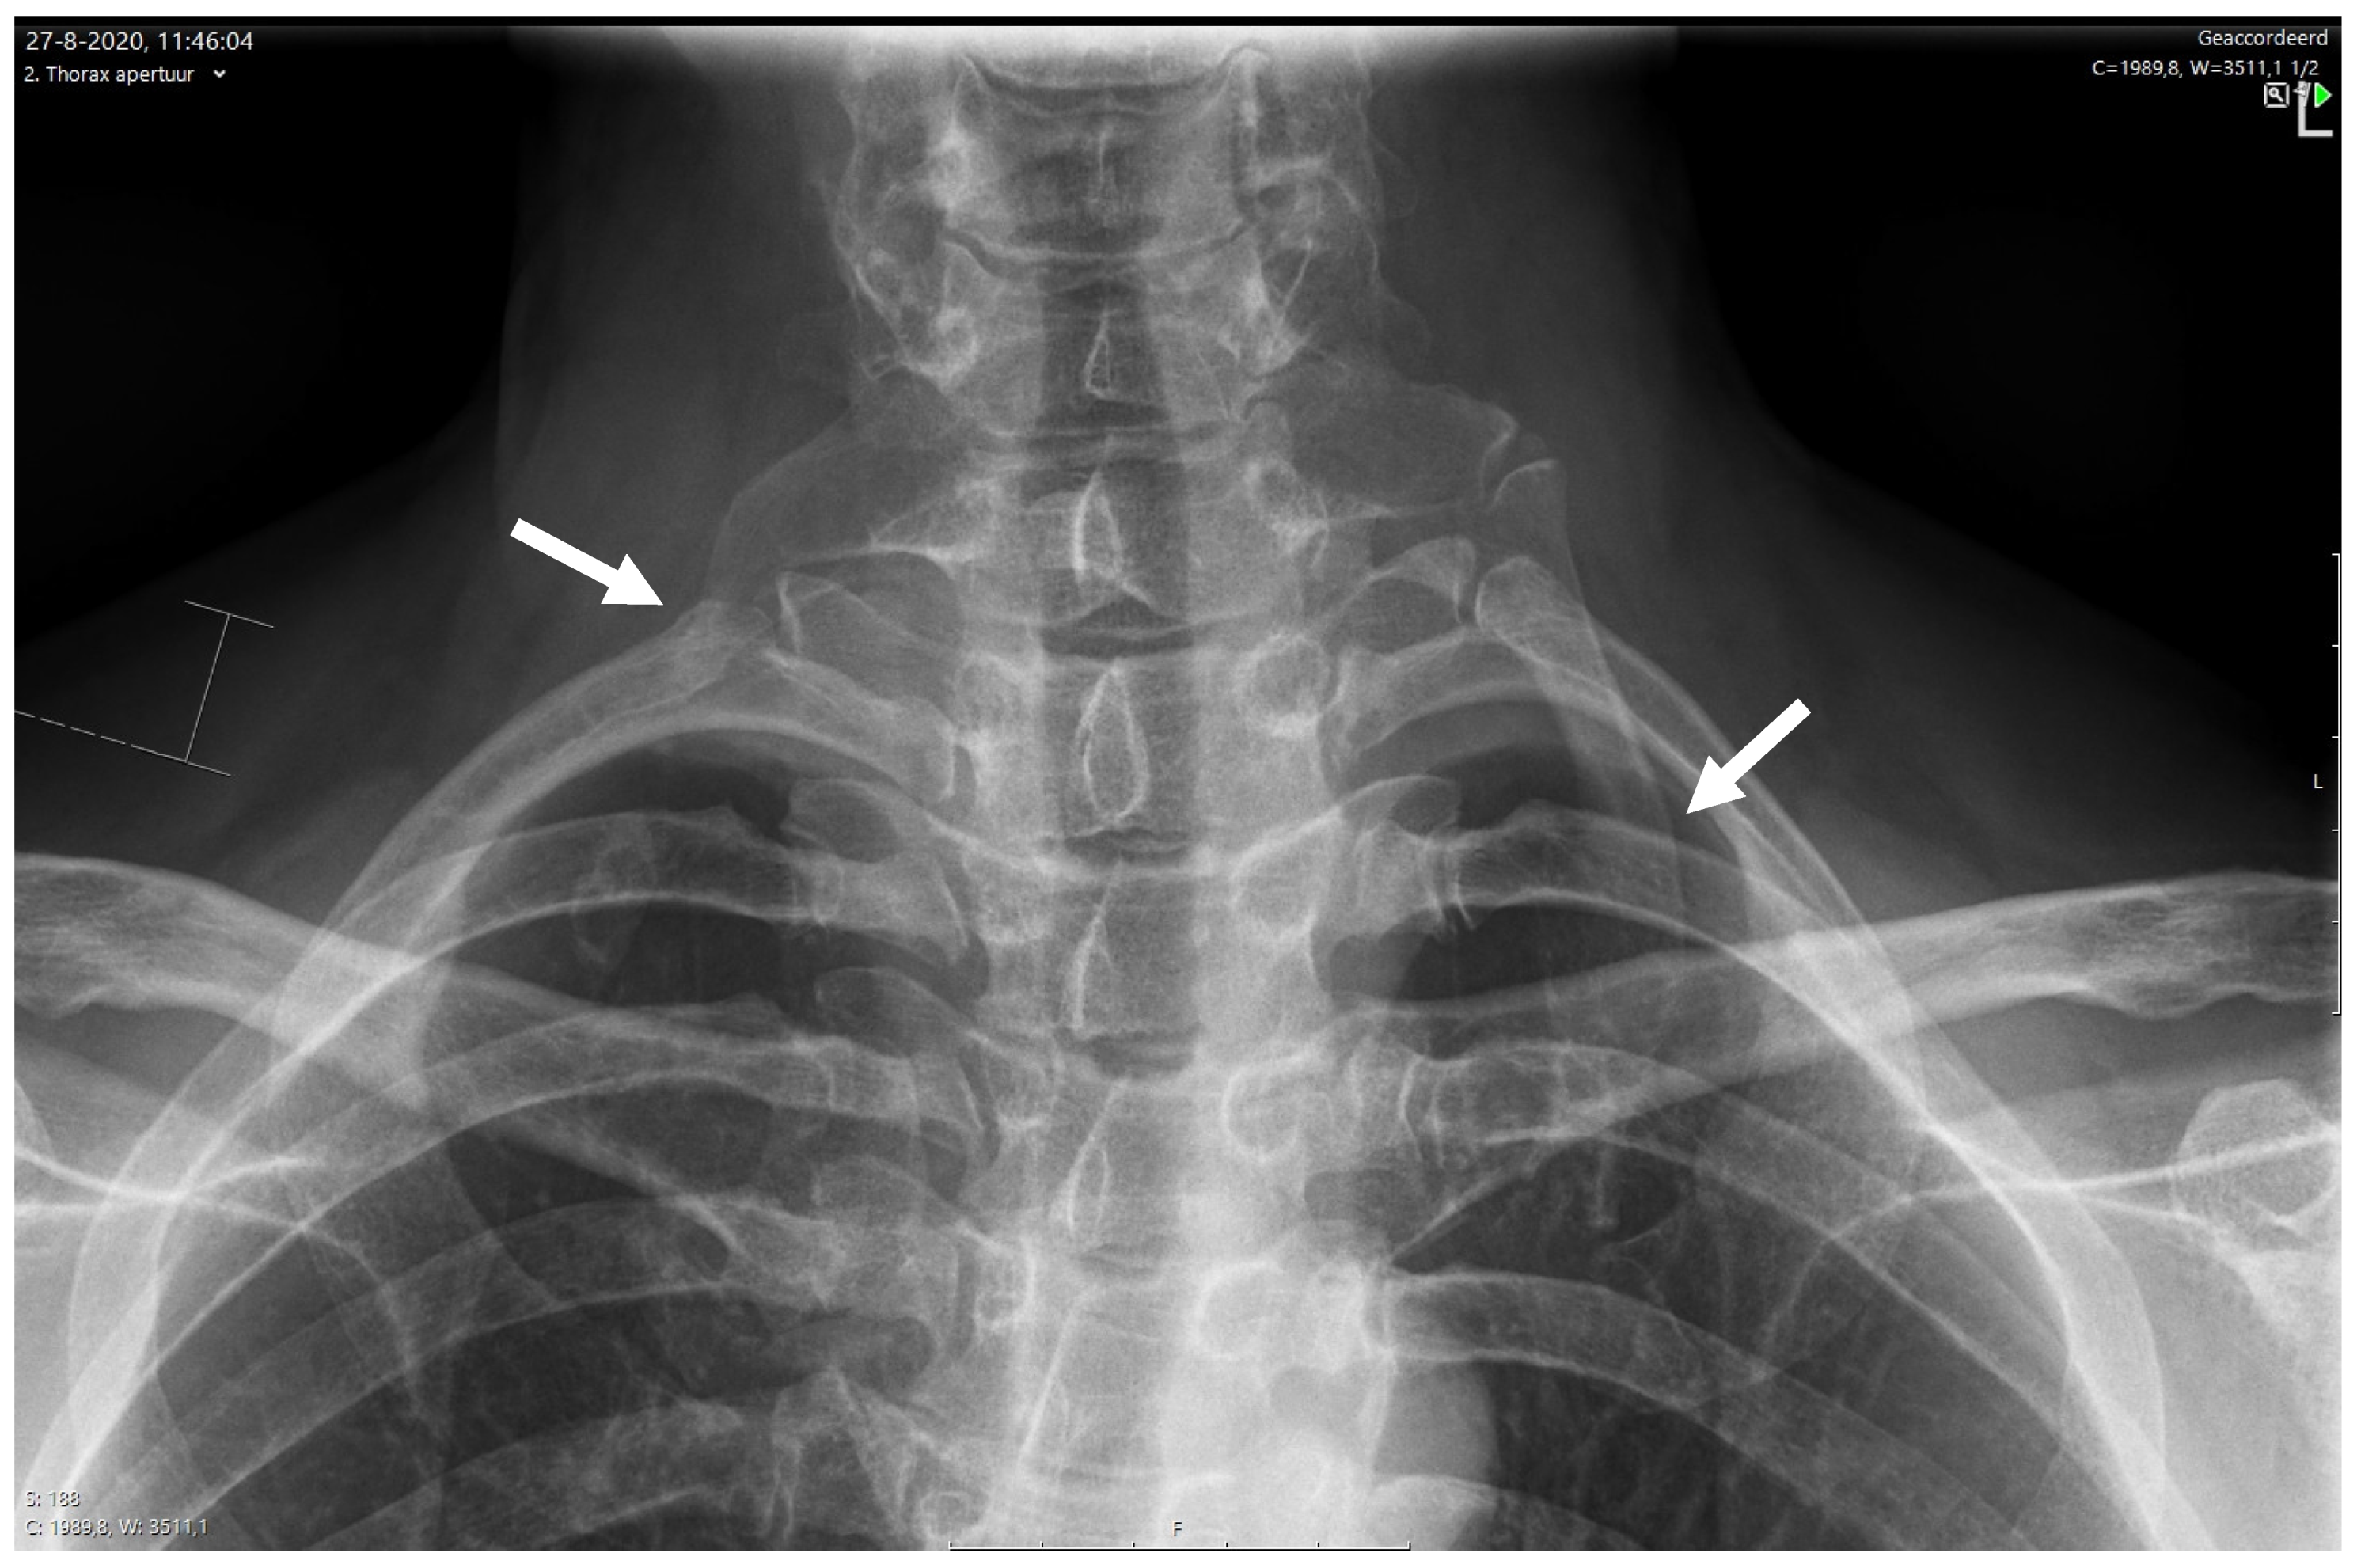

6.3.1. X-ray for NTOS

- Raptis, C.A.; Sridhar, S.; Thompson, R.W.; Fowler, K.J.; Bhalla, S. Imaging of the Patient with Thoracic Outlet Syndrome. Radiographics 2016, 36, 984–1000. [Google Scholar] [CrossRef]